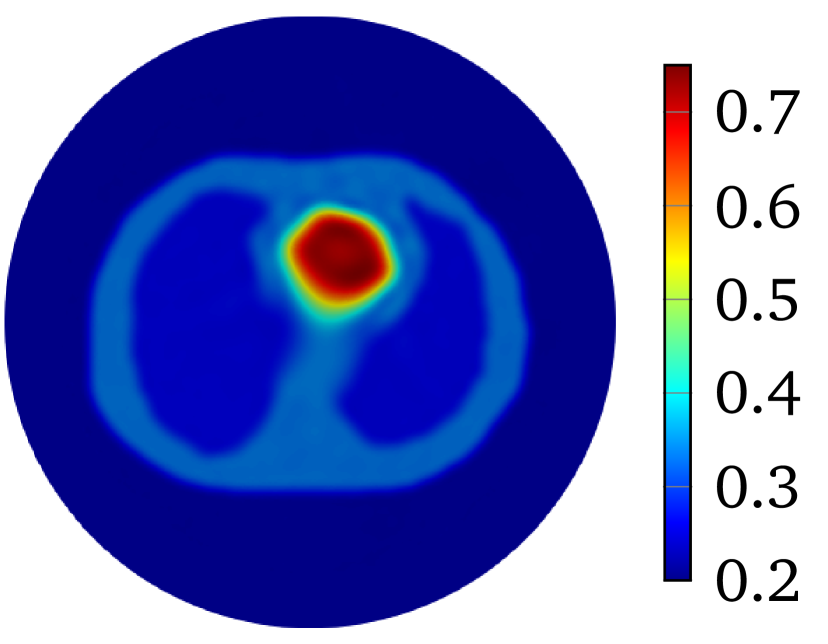

The LM-SCEM algorithm is used to reconstruct the distribution of . The initial guess is given as which is the value of the background tissue. The conductivity in the region for is supposed to be known. The values of are truncated to only update for with . The discontinuity caused by this truncation can be removed by applying (20) properly (either by mollification or simply by replacing the discontinuous values), but it does not cause any numerical problems since is small, so no special treatment was done in the following computation. The values of for the first 15 iterations are shown in Figure 4(a). The relative error is also given in Figure 4(b). With noise, the reconstruction with uniformly converges to with 15 iterations. The reconstructed is shown in Figure 5(a). To achieve a level of , it takes more than 40 iterations. A reconstruction with and is then carried out, but a similar speed of convergence and relative error is observed, result is in Figure 5(b). When the current pattern is further considered into the reconstruction, an obvious improvement of convergence is seen, and a relative error level is achieved with 14 iterations, the conductivity map is shown in Figure 5(c). Therefore, the convergence of LM-SCEM depends not only on the regularization parameter and the scaling parameter , but also on the current patterns for the measurements. Since indicates 0.1% of Gaussian noise in the simulated , the reconstructed result with is already good, and more iterations will not improve the result. To verify, a reconstruction with , and is carried out with (1% noise). Relative errors are shown in Figure 4(b), the reconstruction converges to within 7 iterations, and more iterations did not bring any improvements. The reconstructed result is given in Figure 5(d).